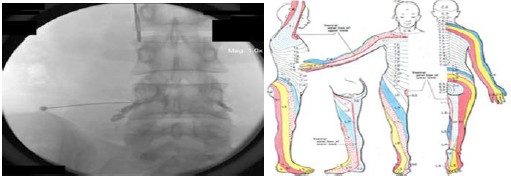

神經根病變:屬於神經根源性疼痛症狀,治療建議可復健、藥物有許多種,例如TCA、SSRI、SNRI、NSAID、肌肉鬆弛劑,當無效時可轉介醫療院所進行神經阻斷治療,通常會先透過X光進行診斷,再進行神經根阻斷術,若有效果可申請健保給付或是自費進行高頻熱凝療法。同時也會建議注射後休息一小段時間,再持續進行復健。

不同型態疼痛診斷及治療-下肢疼痛

神經根病變及週邊神經病變和上肢疼痛的診斷和治療方式類似。

肌筋膜疼痛:最常見的是下背痛,通常為受傷、脊椎側彎、薦髂關節病變等因素相關,口服藥物和復健等保守治療為第一線治療方式,為了改善生活品質可考慮神經阻斷或高頻熱凝治療配合,會有不錯的效果。